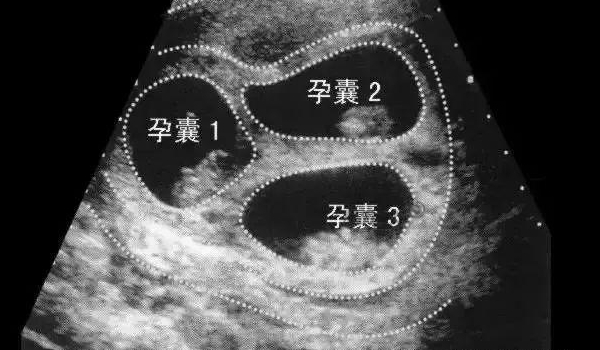

空孕囊本质是胚胎停育的一种表现,多发生在孕6-8周。正常妊娠时,孕囊形成后会逐渐出现卵黄囊、胎芽及胎心,而空孕囊仅存在孕囊结构,始终无胚胎组织分化,或胚胎发育至极早期即停止。其形成与染色体异常、母体激素不足、子宫环境不佳等多种因素相关,属于自然淘汰的一种妊娠异常,并非由单一原因导致。

空孕囊最长存活时长无统一标准,短则数天,长则数周,核心受母体激素水平影响。若母体孕激素、人绒毛膜促性腺激素(HCG)水平仍能维持孕囊形态,可能暂时延缓孕囊萎缩,使其存活1-2周;若激素水平快速下降,孕囊会迅速萎缩、坏死。此外,孕囊自身发育状态也有影响,发育不良的孕囊多在确诊后数天内自然凋亡,少数情况下可能因激素波动出现短暂的形态维持。